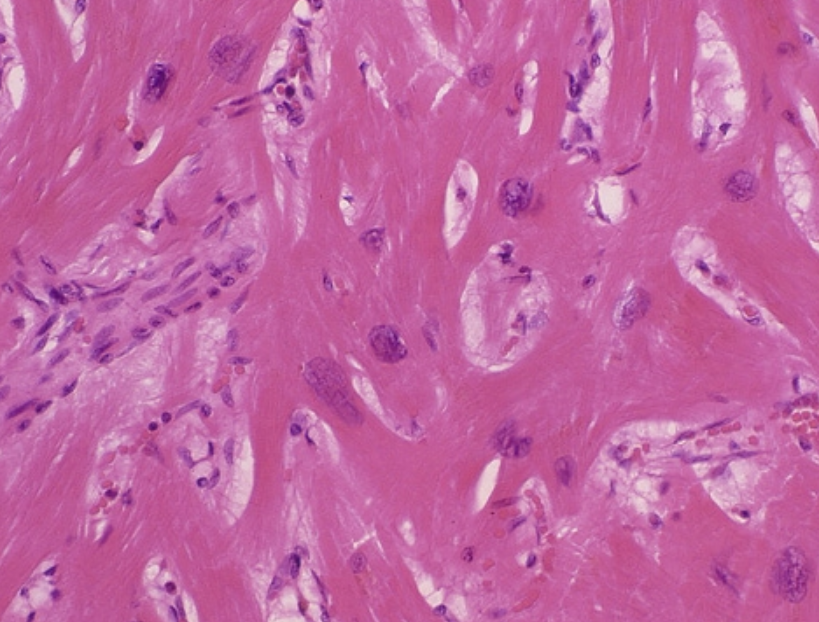

ÆÃȯÀ¿´¶Ú¾É¤ËÃÖ¤±¤ë¿´¶ÚÀ¸¸¡Ê¼Ë¡¤ÎÉÂÍý·×Âà³ØÅª¸¡Æ¤

³ÈÄ¥·¿¿´¶Ú¾É¤Î¿´ÅÅ¿Þ¤ÎÆÃħ¡§

¡¡³ÈÄ¥·¿¿´¶Ú¾É¤ËÆÃ°ÛŪ¤Ê¿´Åſ޽긫¤Ï¤Ê¤¤¡¥¤·¤«¤·¤Ê¤¬¤é¡¤¿´¶Ú¤ÎÀþ°Ý²½¡¤¿´Ë¼¿´¼¼¤Î³ÈÄ¥¡¤»É·ãÅÁƳ·Ï¤Î¾ã³²¡¤¿´ÉÔÁ´Åù¤ËͳÍ褹¤ëÇÈ·ÁÊѲ½¡¤ÉÔÀ°Ì®¤¬Ç§¤á¤é¤ì¤ë¡¥ÆÃ¤Ëº¸¼¼¤Î³ÈÄ¥¡¤Àþ°Ý²½¤¬¿Ê¹Ô¤¹¤ë¤È¡¤º¸¼¼¹âÅŰ̢·º¸¼¼ÈîÂç¡Ê³ÈÂç¡Ë¡¤r Çȸº¹â¡ÊÆÃ¤ËV1¤«¤éV3 ͶƳ¤Îpoor r progression¡Ë¡¤°Û¾ïQÇÈ¡¤QRSÉý±äĹ¡¤º¸Â¦¶»ÉôͶƳ¤Ë¤ª¤±¤ëVAT±äĹ¡¤ µÓ»Þ¥Ö¥í¥Ã¥¯¡¤ ¿´¼¼Æâ¥Ö¥í¥Ã¥¯¡¤ ST-TÊѲ½¤Ê¤É¤¬½Ð¸½¤¹¤ë¡¥º¸¼¼¤Î³ÈÄ¥¤¬¤µ¤é¤Ë¿Ê¹Ô¤¹¤ë¤È¡¤QRSÉý¤¬0.12Éäòͤ¨¡¤º¸µÓ¥Ö¥í¥Ã¥¯½ê¸«¤òÄ褹¤ë¤¬¡¤¤½¤ÎÇÈ·Á¤Ïº¸¼¼³ÈÂç¤òȼ¤ï¤Ê¤¤Ãæ¿õÀ¤Îº¸µÓ¥Ö¥í¥Ã¥¯¤È¤Ï°Û¤Ê¤ê¡¤QRSÇȤËÊ£¿ô¤Înotch¤ò´Þ¤à¤è¤¦¤Ê°Û¾ï¤ÊÇÈ·Á¡ÊËö¾¿À¤Îº¸µÓ¥Ö¥í¥Ã¥¯¡Ë¤È¤Ê¤ë¡¥¤Þ¤¿¡¤º¸¼¼¤ÎÀþ°Ý²½¤¬¶ËÅ٤˿ʹԤ¹¤ë¤È¡¤º¸¼¼¤Îµ¯ÅÅÎϤ¬Äã²¼¾Ã¼º¤·¤Æ¡¤º¸Â¦¶»ÉôͶƳ¤ÎRÇȤ¬ÃøÌÀ¤Ë¸º¹â¤·¡¤SÇȤ¬¼çÂΤζ»ÉôͶƳÇÈ·Á¤ò¼¨¤¹¡Ê±¦µÓ¥Ö¥í¥Ã¥¯Îã¤ò½ü¤¯¡Ë¤È¤È¤â¤Ë¡¤»Í»èͶƳ¤ÏÄãÅŰ̲½¤¹¤ë¤è¤¦¤Ë¤Ê¤ë¡¥°ìÊý¡¤±¦¼¼¤Î³ÈÂ硤°µÉé²Ù¤¬À¸¤¸¤ë¤È±¦Â¦¶»ÉôͶƳ¤ÇTÇȤ¬±¢Å¾²½¤·¡¤¤½¤ì¤¬¤è¤êÃøÌÀ¤Ë¤Ê¤ë¤ÈV4¡¤V5ͶƳ¤Þ¤ÇT±¢Å¾¤¬Çȵڤ¹¤ë¤¬¡¤Æ±»þ¤Ëº¸¼¼³ÈÂ礬¸ºß¤¹¤ë¤È¡¤¤½¤ÎÊѲ½¤ÏÌÜΩ¤¿¤Ê¤¯¤Ê¤ë¡¥

ii¡Ë°Û¾ïQ ÇȤʤé¤Ó¤ËÃæ³ÖÀQ ÇȤξüº¡¡°Û¾ïQ ÇȤϡ¤¾®»ùHCM ¤ÎÌóȾ¿ô¤Ë121)¡¤À®¿Í¤Î25¡Á31¡ó¤Ëǧ¤á¤é¤ì¤ë80)¡¤117)¡¥°Û¾ïQÇÈ·ÁÀ®¤Ë¤Ï¡¤Ãæ³Ö¤ÎÉÔ¶ÑÅù¤ÊÈîÂç¤È¿´¶ÚÊÑÀ¤Î2 ¤Ä¤ÎÀ®°ø¤¬¿ä¬¤µ¤ì¤ë127¡Ë¡¥Á°¼Ô¤ÏÈóÂоÎÀÃæ³ÖÈî¸ü¤Ë¤è¤ë½é´ü¥Ù¥¯¥È¥ë¤ÎÉԶѹդǤ¢¤ê¡¤Éý¤Î¶¹¤¤¿¼¤¤Q ÇȤò¼¨¤·¡¤½é´üÃæ³Ö¥Ù¥¯¥È¥ë¤¬º¸¤«¤é±¦Êý¸þ¤Ë¸þ¤«¤¦¾ì¹ç¤Ë¤ÏV5,6 ¤Ë¡¤¾åÊý¸þ¤è¤ê¤Ç¤¢¤ì¤ÐII¡¤III¡¤aVF ¤ËQ ÇȤ¬·ÁÀ®¤µ¤ì¤ë¡¥Ãæ³Ö¤Ë¸Â¶É¤·¤¿¼ãǯÈîÂçÎã¤Ç°Û¾ïQ ÇȤÎÉÑÅÙ¤¬¹â¤¯117¡Ë¡¤ÈîÂ礬º¸¼¼¼«Í³ÊɤؿÊŸ¤¹¤ë¤«¡¤Ãæ³Ö¤Î¿´¶Ú¤ËÀþ°Ý²½¤¬À¸¤¸¤ì¤Ð¡¤Ãæ³Ö¥Ù¥¯¥È¥ë¤ÎÁêÂÐŪ¸º¾¯¤Ë¤è¤ê¡¤Q ÇȤϸº¹â¤·¡¤HCM ¤Î15¡ó¤Ç¤Ï¾Ã¼º¤¹¤ë¡¥¤Þ¤¿¡¤¿´ÀíÉôÈîÂç·¿¿´¶Ú¾É¤ä±¦¼¼ÈîÂçÎã¤Ç¤Ï¡¤°Û¾ïQ ÇȤòȼ¤ï¤Ê¤¤128¡Ë¡¥¡¡¸å¼Ô¤Ï¡¤¿´¶Ú¤ÎÊÑÀ¡¤Àþ°Ý²½¤Ë¤è¤ë¶É½ê¤Îµ¯ÅÅÎϾüº¤Ç¤¢¤ê¡¤RÇȤθº¹â¤È¤È¤â¤Ë¿·¤¿¤Ê°Û¾ïQ ÇȤ¬½Ð¸½¤¹¤ë¡¥¤³¤ÎQ ÇȤÏÉý¹¤¤¤³¤È¤¬Â¿¤¯¡¤V4-6 ͶƳ¤Ë¤ß¤é¤ì¤ë¡¥ D-HCM (dilated phase of hypertrophic cardiomyopathy: ³ÈÄ¥ÁêÈîÂç·¿¿´¶Ú¾É)¤Ë¿¤¤¡¥

¡¡ST²¼¹ß¤È±¢ÀTÇȤÏ70¢· 95¡ó¤Ëǧ¤á¤é¤ì¤ë¡¥µ¡½ø¤È¤·¤Æ¤Ï¡¤¿´¼¼ÈîÂç¤Ëȼ¤¦¿´ÆâËì²¼¿´¶Ú¤ÎÁêÂÐŪ¿´¶Úµõ·ì¡¤ÈîÂç¿´¶Ú¤ÎºÆÊ¬¶Ë²áÄø¤ÎÃÙ±ä¤Ëȼ¤¦°ì¼¡ÀÊѲ½¡¤Ã¦Ê¬¶Ë²áÄø¤ÎÊѲ½¤Ëȼ¤¦Æó¼¡ÀÊѲ½¤Ê¤É¤¬¿ä¬¤µ¤ì¤ë¡¥¥¹¥È¥ì¥¤¥ó¥Ñ¥¿¡¼¥ó¤¬Â¿¤¤¤¬¡¤Äã²¼¤ÎÄøÅÙ¤ÏÈîÂç¤ÎÄøÅÙ¤ÈÁê´Ø¤·¤Ê¤¤¡¥

¡¡¿´ÀíÉôÈîÂç·¿¿´¶Ú¾É¤Ç¸«¤é¤ì¤ëº¸Â¦¶»ÉôͶƳ¤Î¹âÅṲ̋òȼ¤¦µðÂç±¢ÀTÇȤÏV3 ¢· 5¤òÃæ¿´¤Ë¡¤1.0mV°Ê¾å¤ÇÂоÎÀ¤ò¼¨¤·¡¤¤·¤Ð¤·¤ÐST²¼¹ß¤ò¤ß132¡Ë¡¤¿´ÀíÉôÈî¸ü¤ÎÄøÅÙ¤¬¶¯¤¤¤Û¤É¿¼¤¯¤Ê¤ë133¡Ë¡¥¿´ÀíÉôÈîÂç·¿¿´¶Ú¾É¤Î70 ¡ó¤Ç¤Ï¡¤¹âÅṲ̋äµðÂç±¢ÀTÇȤϷвá¤È¤È¤â¤Ë¸º¾¯¡¤¾Ã¼º¤·124¡Ë¡¤¤½¤Î¸¶°ø¤ÏÈîÂç¿´¶Ú¤ÎÊÑÀ¡¤Àþ°Ý²½¤Ëȼ¤¦Âà¹ÔÀÊѲ½¤È¹Í¤¨¤é¤ì¤ë¡¥

ÈîÂç·¿¿´¶Ú¾É1 Dagger-like Q Waves

ÈîÂç·¿¿´¶Ú¾É2 Giant T wave inversion

ÈîÂç·¿¿´¶Ú¾É3 Classic HCM with asymmetrical sptal hypertrophy